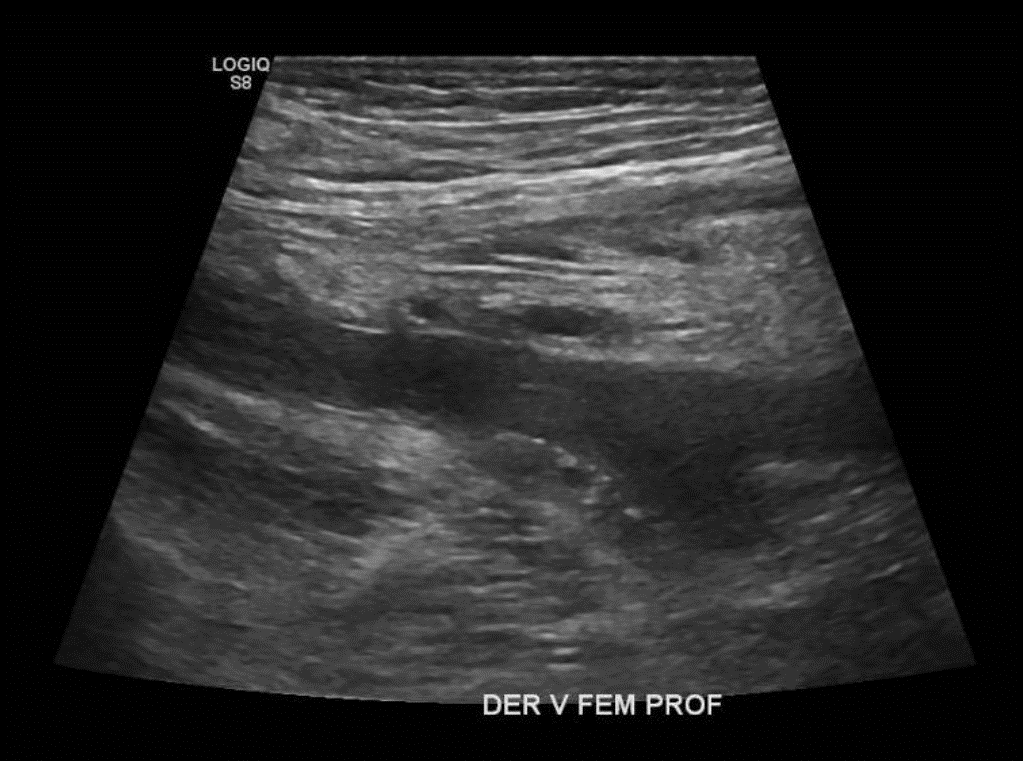

• Desde la VFC se visualiza contenido ecogénico interno, no compresible y sin señal al Doppler Color sugerente de Trombo que se extiende por toda la cara posterior del muslo comprometiendo a la Vena Femoral Profunda. Vena Femoral Superficial permeable.

Hallazgos: Piel y tejido subcutáneo sin alteraciones. Material ecogénico endoluminal en vena femoral común, vena femoral superficial y profunda, con ausencia de flujo y compresibilidad, compatible con trombosis venosa profunda en evolución. Planos musculares de aspecto ecográfico conservado, sin evidencias de desgarros fibrilares. Engrosamiento disminución de ecogenicidad inserción proximal de los isquiotibiales, sin desgarros. No se observan lesiones nodulares ni quísticas. Contornos óseos visualizables regulares. Impresión

Diagnóstico: Hallazgos compatibles con trombosis venosa profunda de vena femoral común, vena femoral superficial y profunda. Es indispensable evaluación clínica de urgencia. Entesitis proximal de los isquiotibiales.